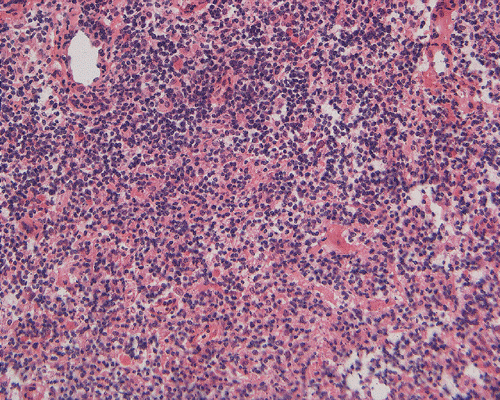

Microscopically, the morphology is similar to the corresponding type of lymphoma that occurs in other parts of the body. The neoplastic cells demonstrate a classic perivascular infiltration that dissects the perivascular reticulin network. Geographic necrosis may be seen when tumors become confluent, with perivascular islands of viable tumor cells surrounded by large regions of coagulative necrosis. As most of the PCNSL are of diffuse large B-cell type, the neoplastic cells are typically highly pleomorphic and large. Low-grade lymphomas are relatively uncommon.

Their immunohistochemical profiles are similar to lymphomas that occur outside the central nervous system. Intraoperative recognition of an atypical lymphoproiferative lesion is important as fresh tissue can be sent for flow cytometry which is often an important adjunct for correct diagnosis.